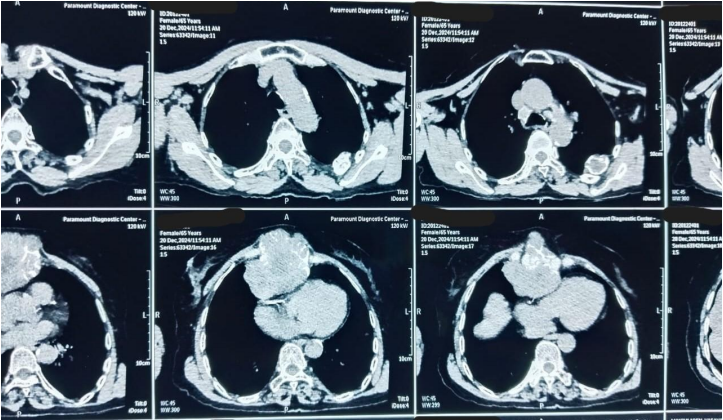

A 71-year-old female presented at Bankers Superspeciality Hospital complaining of swelling over the right side of the face and upper neck region, with localised swelling over the sternum. She was asymptomatic 5 months back as she gradually noticed swelling over her right side of her face and upper neck region, which gradually increased in size. In the past (2018), she had surgery at a local hospital, query for parotid surgery; no documents were available ( surgery note and histopathological report). On inspection and palpation, 8*7cm hard proliferative, lobulated growth present over the right side upper neck region, not fixed to underlying structures, crossing midline of the face with no ulceration present over skin (Image 1). No neck nodes were palpable. No sign of facial palsy present. Localised mass of 6*5cm was present over the right side sternum, which was fixed to the underlying bone (Image 2). No skin ulceration was present over sternum region and no axillary nodes were palpable. The performance status of the patient was ECOG 1. Computed tomography of Neck and chest (Plain + Contrast) suggestive of large heterogeneously enhancing lobulated solid cystic lesion seen in right submandibular and upper internal jugular regions and right submental region anterior to right sternocleidomastoid muscle, size of 94(W)*76(AP)*79.6(CC)mm, with mild compression on right IJV. Approx 78*75*92mm soft tissue lesion involving sternum causing osteolytic destruction extending into the anterior mediastinum displacing heart and other structures posteriorly. A few variable-sized soft tissue density nodules scattered throughout both lungs (Image 3 & Image 4). Trucut Biopsy from Right submandibular region s/o pleomorphic adenoma ( composed of epithelial tubules and myoepithelial cells in abundant chondromyxoid stroma) (Image 5 & Image 6). Trucut Biopsy from sternal mass suggestive of malignant tumor, likely to be sarcoma, chondrosarcoma is a possibility. Further Immunohistochemistry was done which suggestive of lesional cells with chondroid type appearance and matrix with positive for AE1/3, CK7 and S100 with KI-67 2-3% favouring Benign metastasizing pleomorphic adenoma (Image 7 & Image 8). PETCT scan was done, which suggestive of FDG avid heterogenously enhancing lobulated soft tissue mass involving right submandibular and submental region 8.6(AP)*7.3(TS)*8.9(CC) ; SUV max 8.6. Medially involving the Right submandibular gland Indenting onto right SCM and strap muscles, Superioly lesion is infiltrating inferior lobe of right parotid gland, overlying skin is involved with no obvious erosion. FDG avid lytic destructive lesion are noted involving sternum, left fifth rib, D12 and L3 vertebrae. Sternal lytic destructive lesion is present with soft tissue compenent with calcification of 8.2*7.2*10.5cm; SUV max 5.9. Soft tissue component is extending into anterior mediastinum and is seen infiltrating right middle lobe lung parenchyma. Left fifth rib is assosciated with  FDG avid enhancing soft tissue component 2.6*2.3cm; SUVmax 6.5 (Figure 9). On PETCT Scan report with skeletal metastasis, in multidisciplinary tumor board discussion, the case was discussed and decided to give palliative chemotherapy.

Figure 3: Computed Tomography with contrast of Head and Neck

Figure 4: Computed Tomography with contrast of Chest